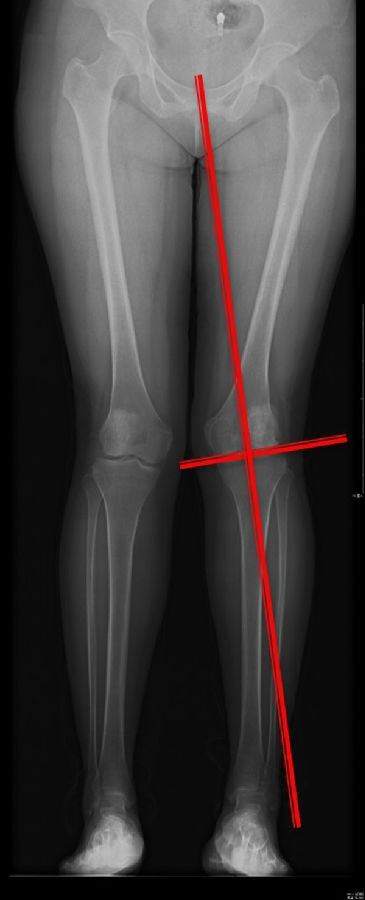

步骤二:判断畸形部位

量股骨远端外侧角和胫骨近端内侧角,判断畸形在股骨、胫骨还是关节内。此患者股骨侧有畸形,LDFA=76°,MPTA=81°,无关节内畸形。